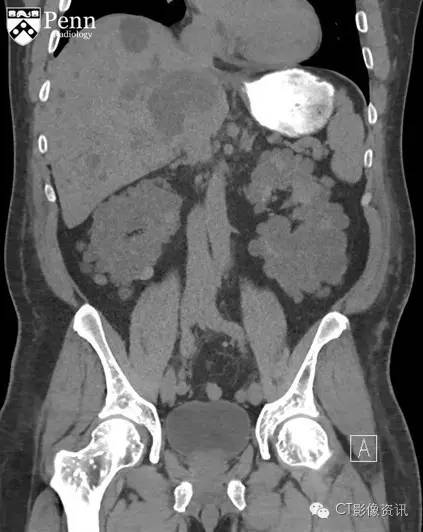

腹盆部冠状位以及轴位CT影像骨窗显示多个边界清晰的细小硬化灶呈现圆形、卵圆形以及线样;其直径从几毫米到一厘米不等,分布在股骨以及髋臼顶部;不伴有骨膜反应和骨质破坏。在软组织窗冠状位CT图像显示双侧肾影增大,伴随大量囊样密度影;此外在肝脏也可见囊样密度;可能为常染色体显性遗传多囊肾后遗症导致。

最终诊断:骨斑点症